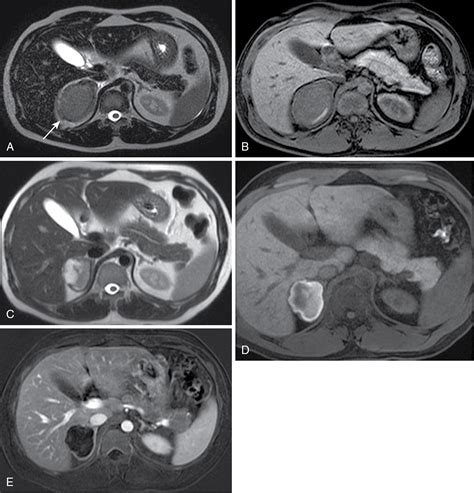

• Imaging Review: A radiologist will analyze the "washout" characteristics of the nodule on a CT scan to estimate the lipid content within the tissue.

Differentiating Between Benign and Malignant Nodules

Differentiating between a harmless adenoma and a malignant tumor is the primary objective of your medical team. Benign adrenal adenomas are the most frequent finding. These are generally small, stable over time, and lipid-rich. Conversely, adrenocortical carcinoma is a rare form of cancer that usually presents as a larger, irregularly shaped mass. Imaging techniques such as contrast-enhanced CT scans, MRI, or even PET scans may be utilized if the initial findings are inconclusive or if the nodule demonstrates suspicious features.